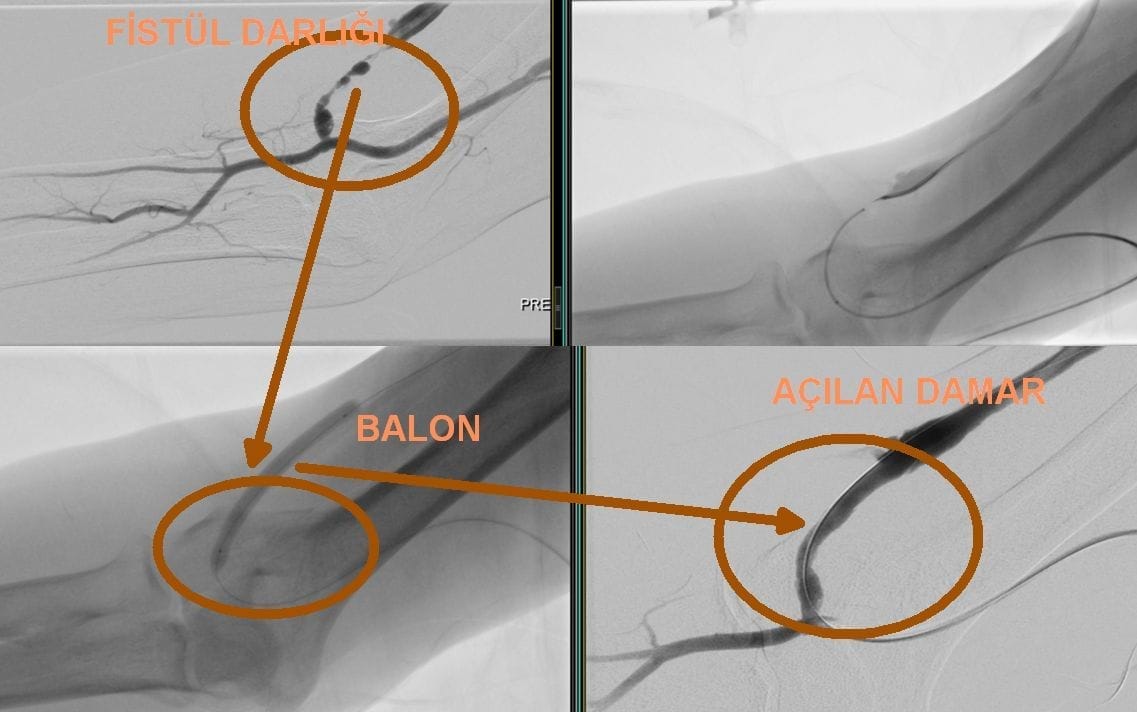

Deschiderea blocajelor fistulei de dializă prin angiografie

Blocajele fistulelor, frecvent întâlnite la pacienții dializați, sunt tratate eficient prin angiografie. Această metodă, datorită naturii sale minim invazive, implică un risc mai scăzut pentru pacienți și asigură o recuperare rapidă. În timpul procedurii, un cateter este introdus în interiorul vasului până la zona blocajului. Metodele utilizate pentru deschiderea blocajului sunt următoarele:

- Anjiyoplastia cu balon: Se plasează un balon în zona blocajului, iar balonul este umflat pentru a dilata vasul.

- Implantarea de stent: Pentru a preveni reblocarea vasului, se introduce un stent metalic în zona dilatată. (stent)

- Trombectomie: Cheagul de sânge este dizolvat cu ajutorul unor instrumente speciale sau medicamente pentru a redeschide vasul.

Aceste metode sunt alese și aplicate în funcție de starea pacientului. Astfel, funcționalitatea fistulei necesare pentru dializă este păstrată. Intervențiile efectuate prin angiografie permit continuarea tratamentului de dializă, îmbunătățind calitatea vieții pacienților.